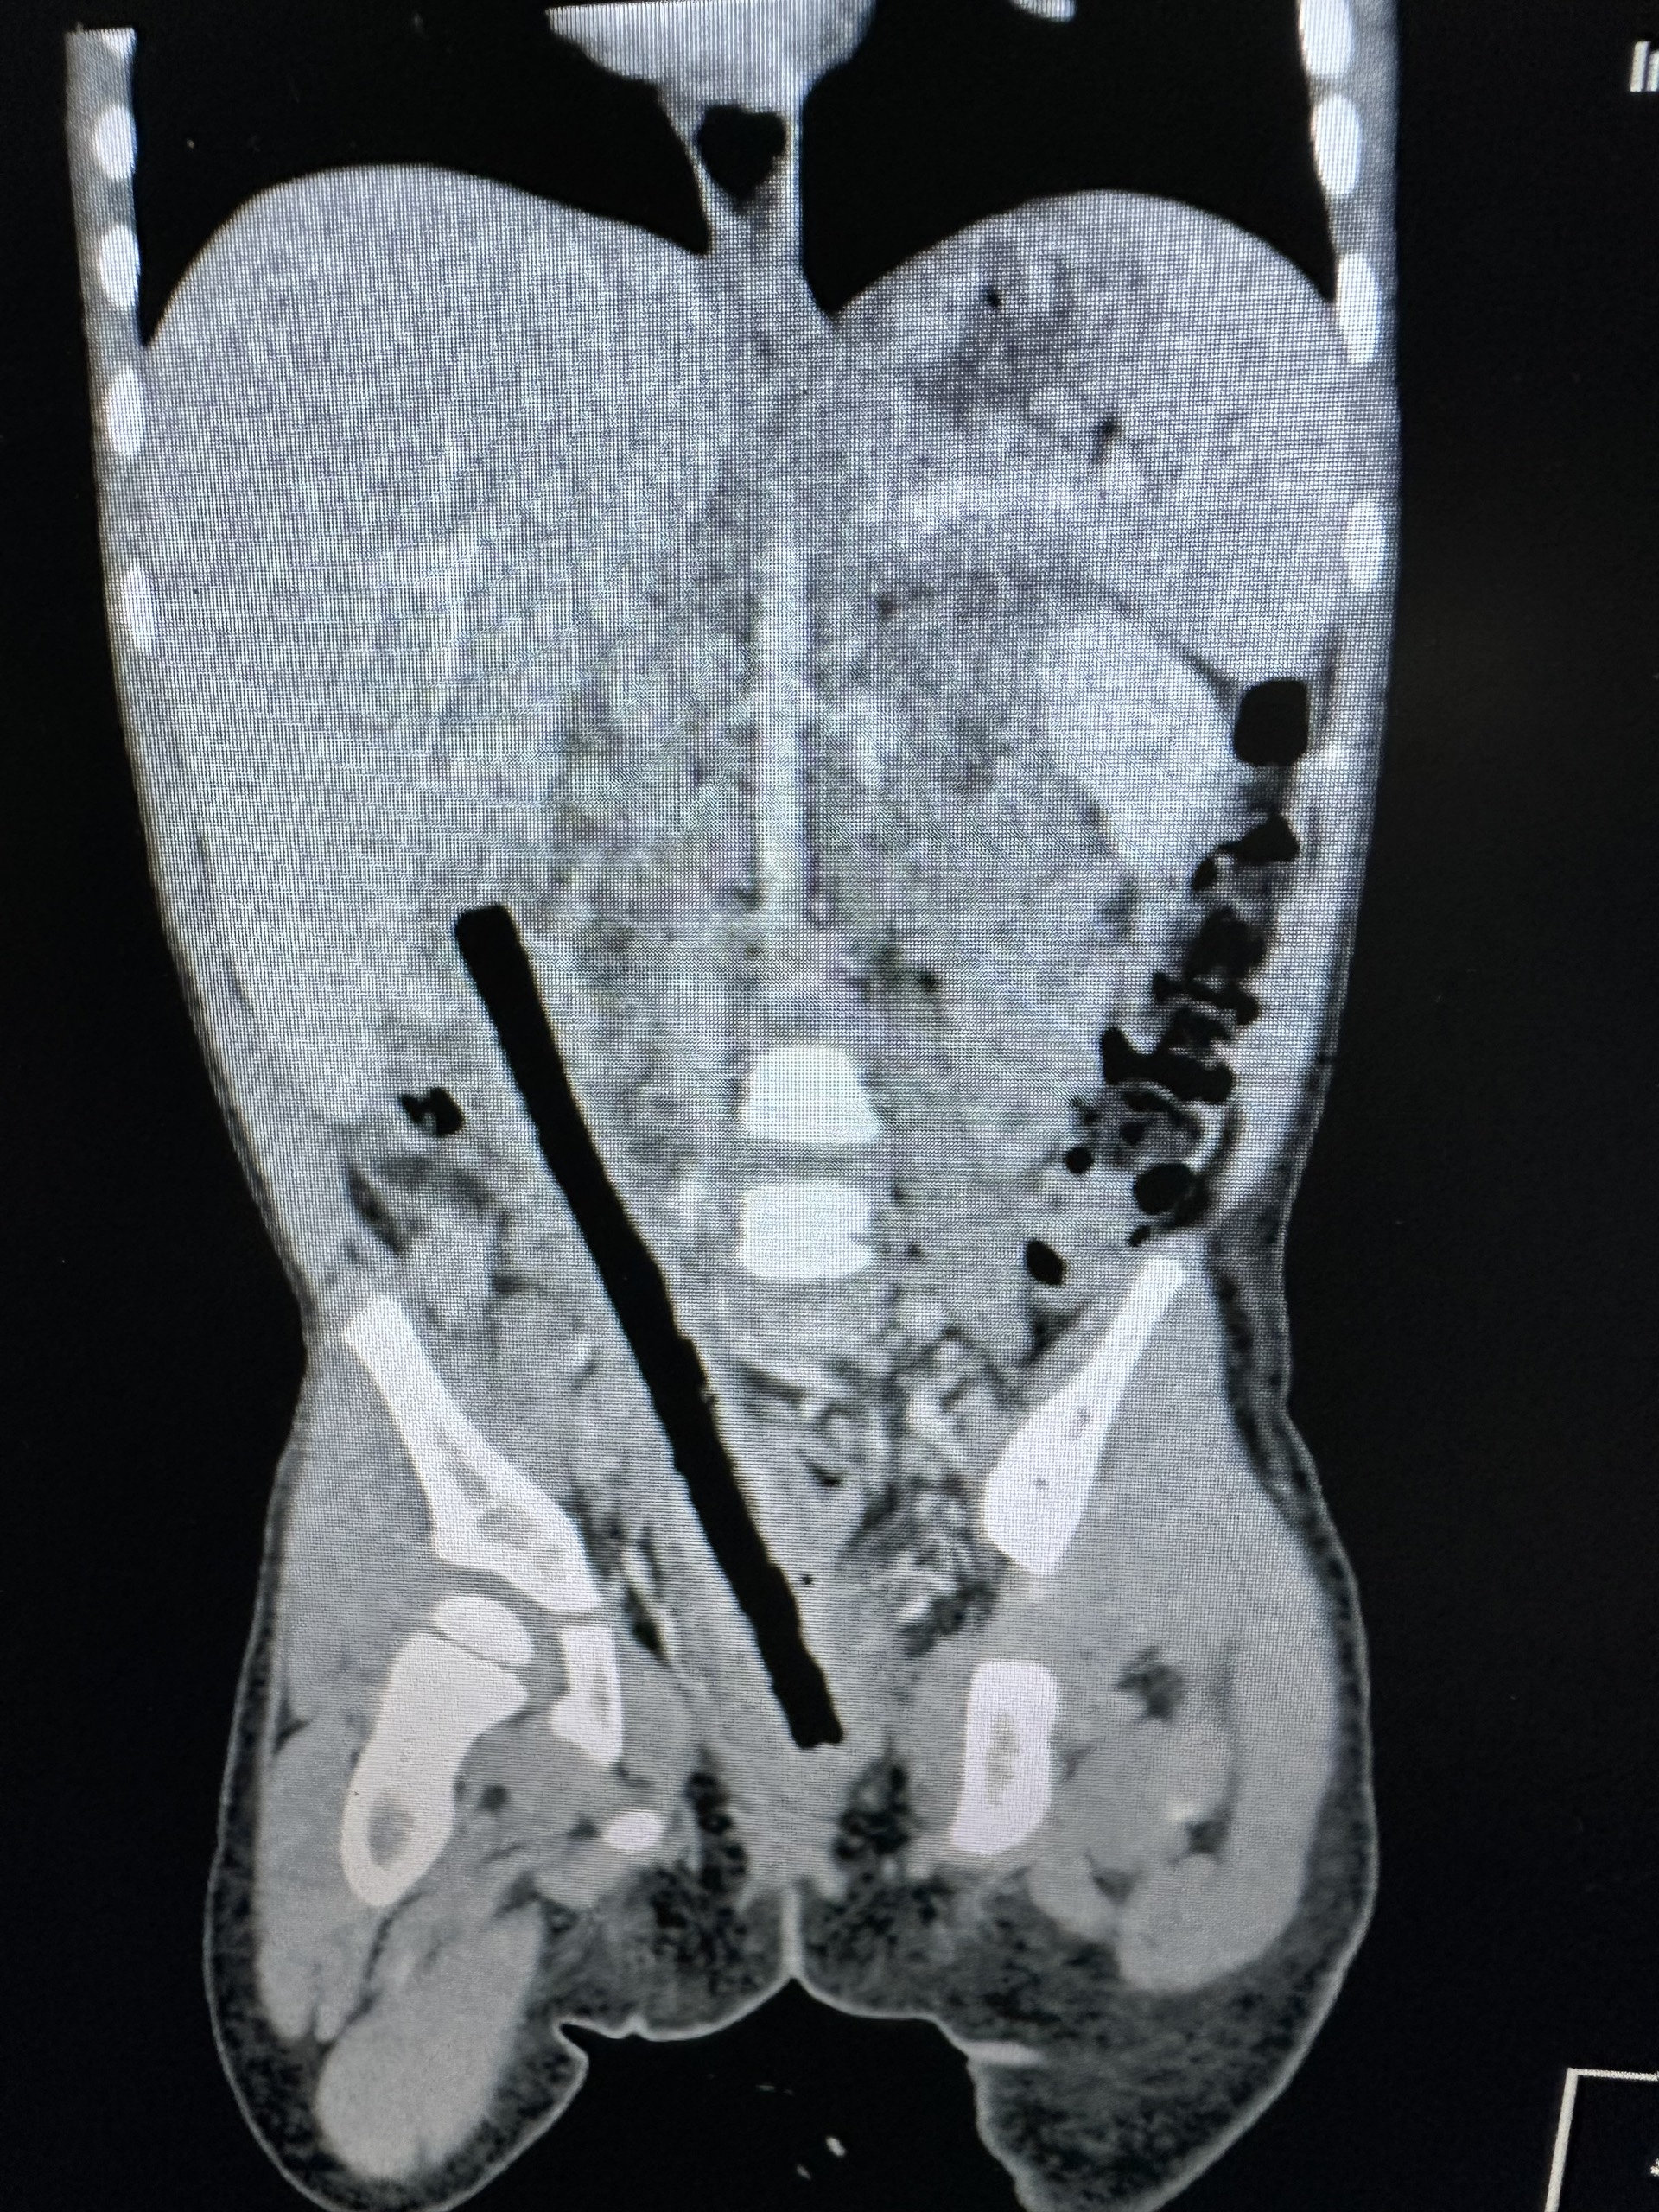

Theo BSCK1 Nguyễn Hiền, Khoa Ngoại tổng hợp - Bệnh viện Nhi Đồng 2, kết quả CT scan cho thấy trong ổ bụng bệnh nhi có dị vật kích thước 1x16 cm nằm vùng từ trực tràng đến gan.

Ê-kíp nội soi xác định dị vật đâm xuyên trực tràng, ruột non và tá tràng viêm dính nhiều, gây khó khăn cho phẫu thuật. Các bác sĩ tiến hành mổ mở bóc tách dọc theo dị vật, tách dính toàn bộ ruột, tránh làm tổn thương các mạch máu thần kinh và niệu quản, hạn chế các tổn thương các bộ phận khác.